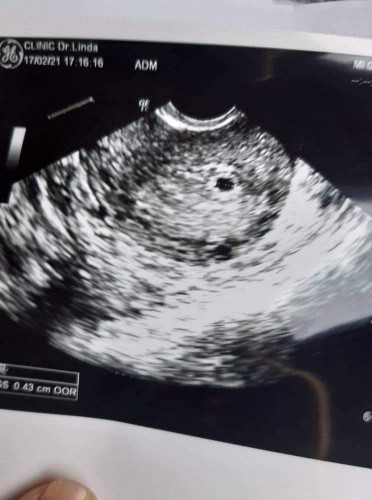

โรงบาลบอกว่าแท้ง คลินิกบอกท้อง1เดือน